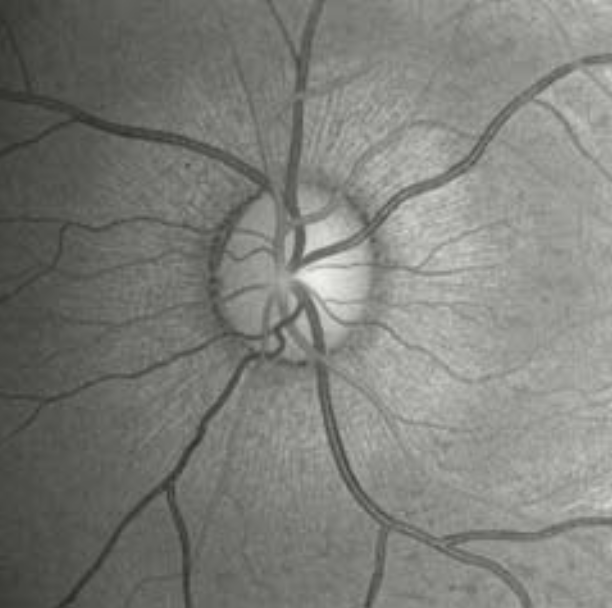

Figure 3, taken from [3], shows the view of the retina, with the optic disk in the middle. The are no rods and cones, which are two fundamental elements for our vision system, in the optic disk creating thus a blind spot. We are not usually aware of the blind spot but a simple test can highlight it.

Fig. 3 – Back of the eye with the optic disk, image taken from [3].